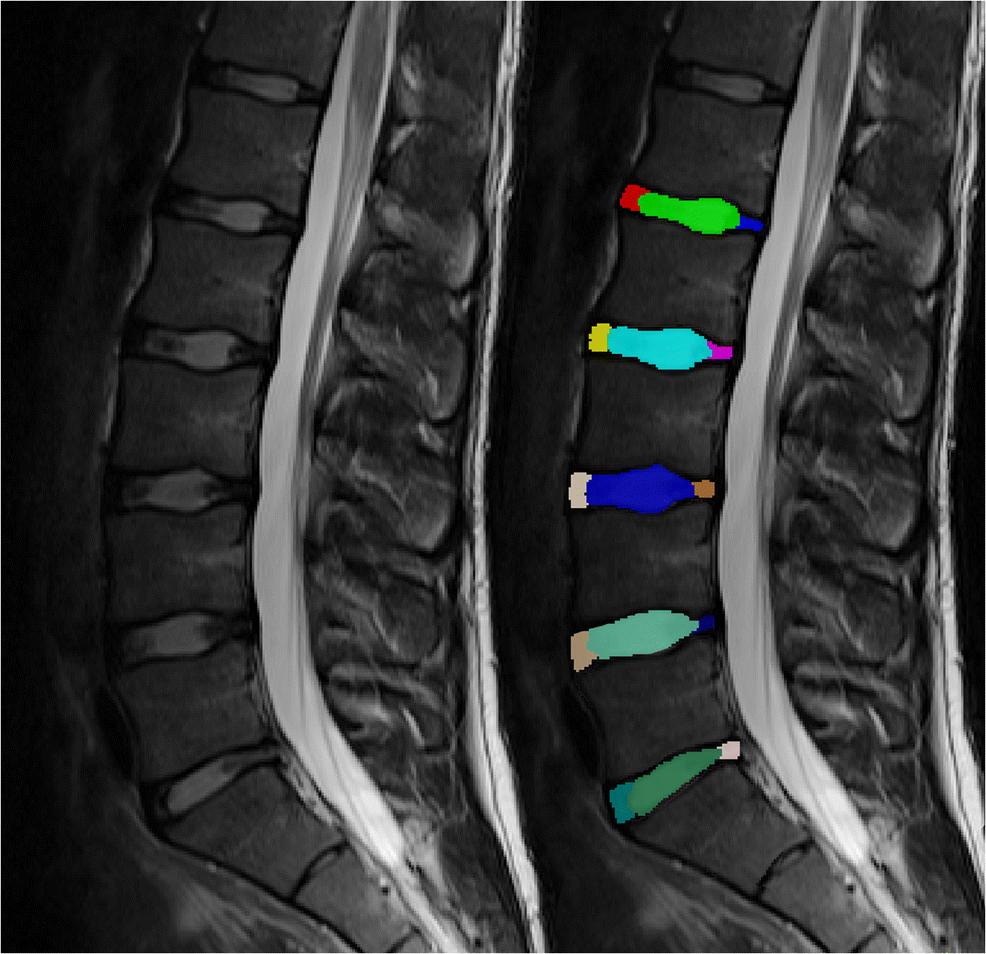

The resulting images were manually segmented on the sagittal T2-weighted TSE sequence using the four most central slices by a radiology resident with 5 years of experience in musculoskeletal imaging using ITK-Snap [18]. First, a strict geometrical order was followed labeling the anterior and posterior 20% as annulus fibrosus with the central 60% of the diameter representing the nucleus pulposus. This was then manually refined depending on the individual discs. An example is depicted in Fig. 1. Individual labels for each discs’ ventral and posterior annular region and the nucleus pulposus of every of the five lumbar discs were drawn. Using Elastix [19], the segmentation was then copied over to the T2 maps after successful automatic co-registration.

Fig. 1

Sagittal T2-weighted contrast (left) with a color-coded overlay visualizing the segmentation done in ITK-SNAP (right). Every intervertebral disc was segmented in three individual regions of interest (ROIs): ventral annulus fibrosus, nucleus pulposus, and posterior annulus fibrosus. This case shows an annular tear in L5/S1